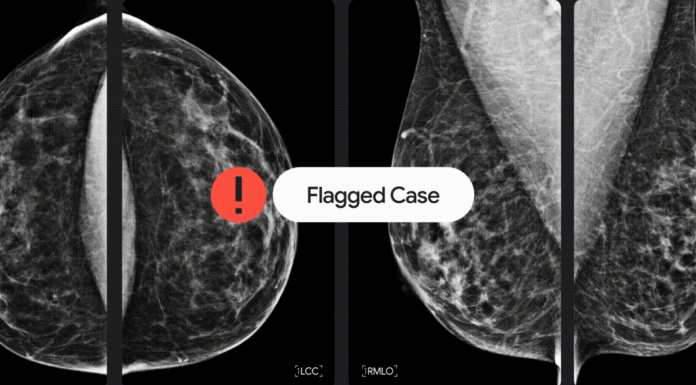

Google Health s'intéresse au cancer du sein, l'un des plus fréquents (2 261 419 nouveaux cas en 2020 selon Cancer.net) depuis plusieurs années. En 2017, la société avait publié un article démontrant comment des modèles d'IA peuvent détecter avec précision le cancer du sein métastatique à partir d’échantillons de ganglions lymphatiques. Ses travaux se sont ensuite portés sur le dépistage du cancer du sein à un stade précoce et en collaboration avec des collègues de DeepMind, du Cancer Research UK Imperial Centre, de la Northwestern University et du Royal Surrey County Hospital, a formé et ajusté un modèle sur un ensemble de données représentatif composé de mammographies anonymisées de plus de 76 000 femmes au Royaume-Uni et de plus de 15 000 femmes aux États-Unis, pour voir s’il pouvait dépister les signes de cancer du sein dans les scans.

Le modèle publié dans une recherche sur Nature a ensuite été évalué sur un ensemble de données anonymisées distinct de plus de 25 000 femmes au Royaume-Uni et de plus de 3 000 femmes aux États-Unis : il a produit une réduction de 5,7 % des faux positifs aux États-Unis et de 1,2 % au Royaume-Uni et une réduction de 9,4 % des faux négatifs aux États-Unis et de 2,7 % au Royaume-Uni.

Alors que les experts humains avaient accès aux antécédents des patients et aux mammographies antérieures, le modèle ne traitait que la mammographie anonyme la plus récente sans aucune information supplémentaire et a pourtant, selon Google Health, surpassé les experts individuels lors de la prise de décision pour identifier avec précision le cancer du sein.